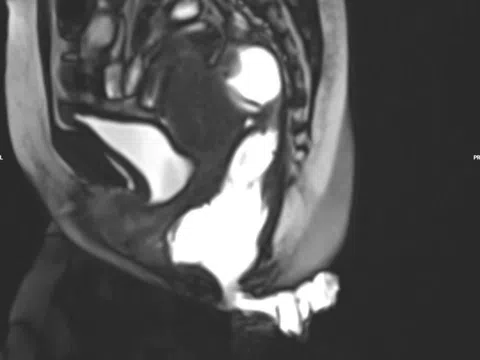

Đau tức hạ sườn, ăn kém, sút cân… là dấu hiệu bệnh gì?

U máu gan là dị dạng mạch máu bẩm sinh và là khối u lành tính hay gặp nhất ở gan. Nhiều người nhập...